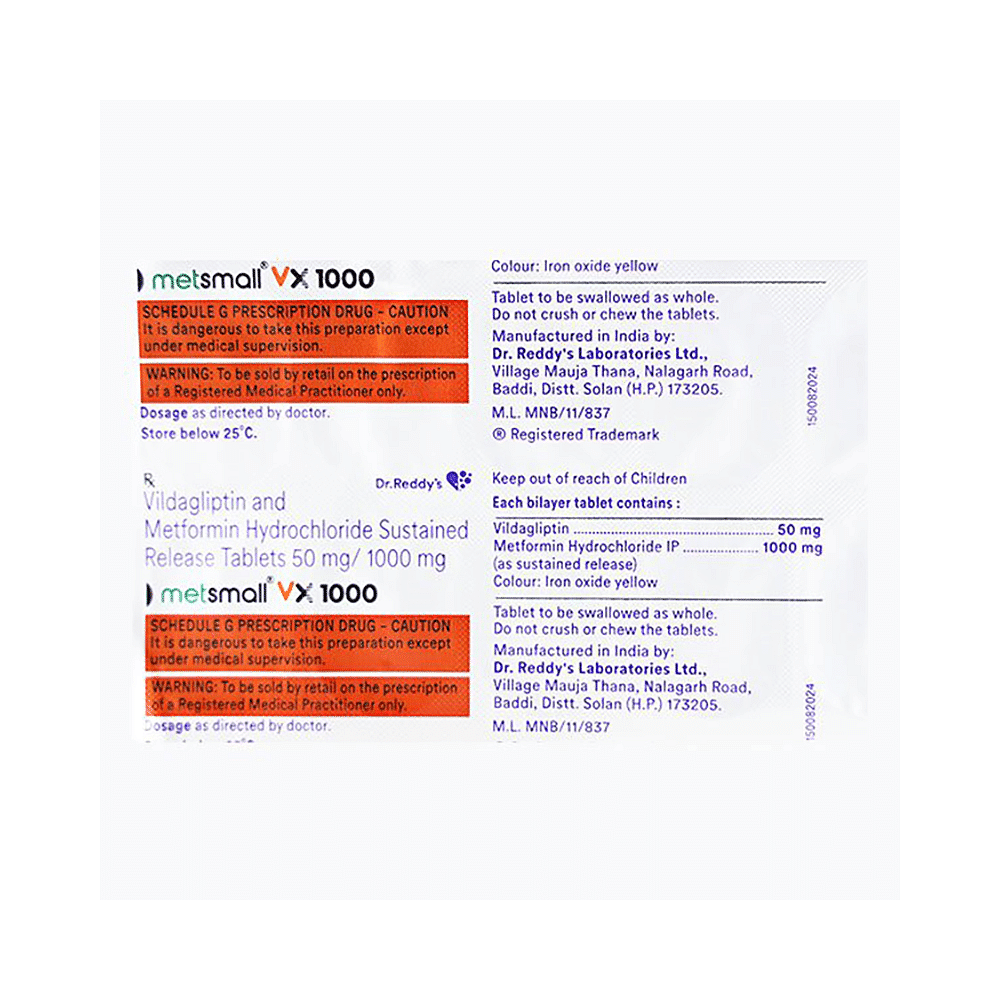

Metsmall VX 1000 Tablet SR